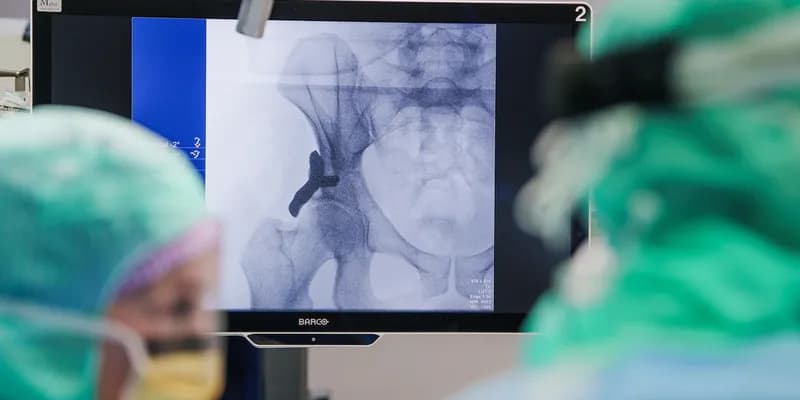

El Hospital Anna, ubicado en Geldrop (Noord-Brabant), ha realizado con éxito la primera operación en humanos utilizando un implante de cadera impreso en 3D.

El procedimiento se llevó a cabo a un paciente de 36 años que sufre de displasia de cadera, una condición en la que la cavidad de la articulación está mal formada, causando dolor y movilidad limitada.

El implante fue diseñado específicamente para adaptarse a la anatomía única del paciente y busca mejorar la estabilidad de la articulación, reducir el dolor y acelerar la recuperación en comparación con los métodos quirúrgicos tradicionales.